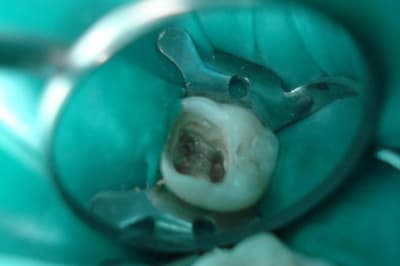

Patiente de presque 18 ans.

Dévitalisation pour pulpite stade 3 de Baume faite en une séance de 3h dans les règles, au protaper.

Séance suivante : nous prévoyons une reconstitution coronoraiculaire avec un matériau inséré en phase plastique, ou RMIPP, ou SC33, ou RCR foulée avec tenon intracanalaire, ou autres appellations si je me trompe.

Mon protocole : mordançage de l'intérieur de la chambre et des canaux à l'acide orthophosphorique 37%

- tenon fibré calibré après forage canal distal puis rinçé à l'alcool et mordancé 20 sec,

- rinçage abondant des 2

- engluage du tenon d'un composite dual, ici le Variolink d'Ivoclar (j'ai eu des échos du SuperBond comme étant pas mal aussi, effet amortisseur entre autres...référence Michel Degrange)

- Insertion puis polymérisation primaire

- comblement du fond par un compo fluide + poly

- Composites de teinte adaptée en plusieurs incréments ensuite pour obturer la couronne + poly

- Polissage

En mon ame et conscience, 3 parois + 1 mésiale présente mais fine, j'ai opté pour cela.

(mes photos : radio ortho et excentrée, "vue de dessus", tenons de chez Anthogyr, mordançage et tenon, et malheur de malheur pas de photo du résultat car plus de batterie dans ce satané appareil.=